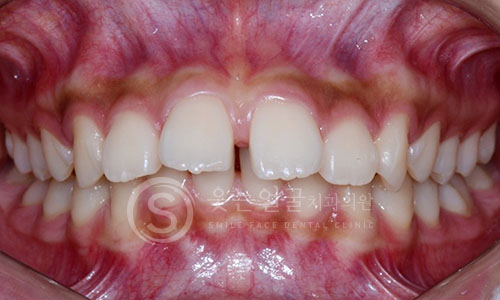

한눈에 보는

임플란트 전후사진